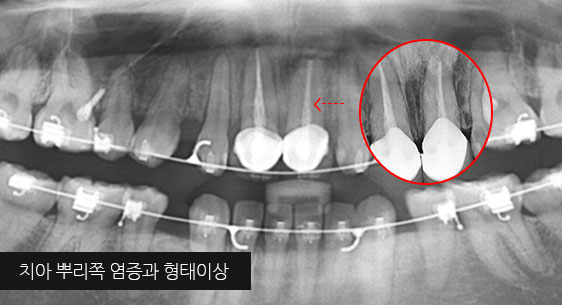

치아 뿌리 주변 염증과 치조골이 녹아내려 통증과 더불어 치아가 흔들리는 상태로 내원한 환자입니다. 우선 큐렛으로 잇몸 속 치석을 제거하였습니다. 뿌리 주변 염증은 신경관을 소독하고 약재를 삽입하는 신경치료를 시행하였습니다.

치근단 염증

신경관 소독

신경관 약재삽입

약재주입 후 반응